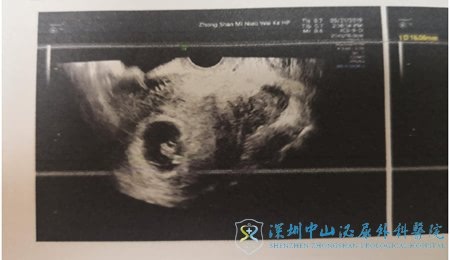

2019年5月12日,孕后第一次B超,一切正常,“现在是确定宝宝在宫内,都发育正常的吧,”看到徐医生肯定的点头,Linda自语道,“试管也没像传说中的这么恐怖啊”。

2019年5月19日,孕后第二次B超,宝贝已经14mm长了,每天在妈妈肚子里茁壮成长,Linda轻松的和徐士儒医生聊到:“早知道试管这么简单,一点也不痛,我就不拖这么久了!网上把试管写的好恐怖,把那么多女性都吓得不敢走进生殖中心的大门。”